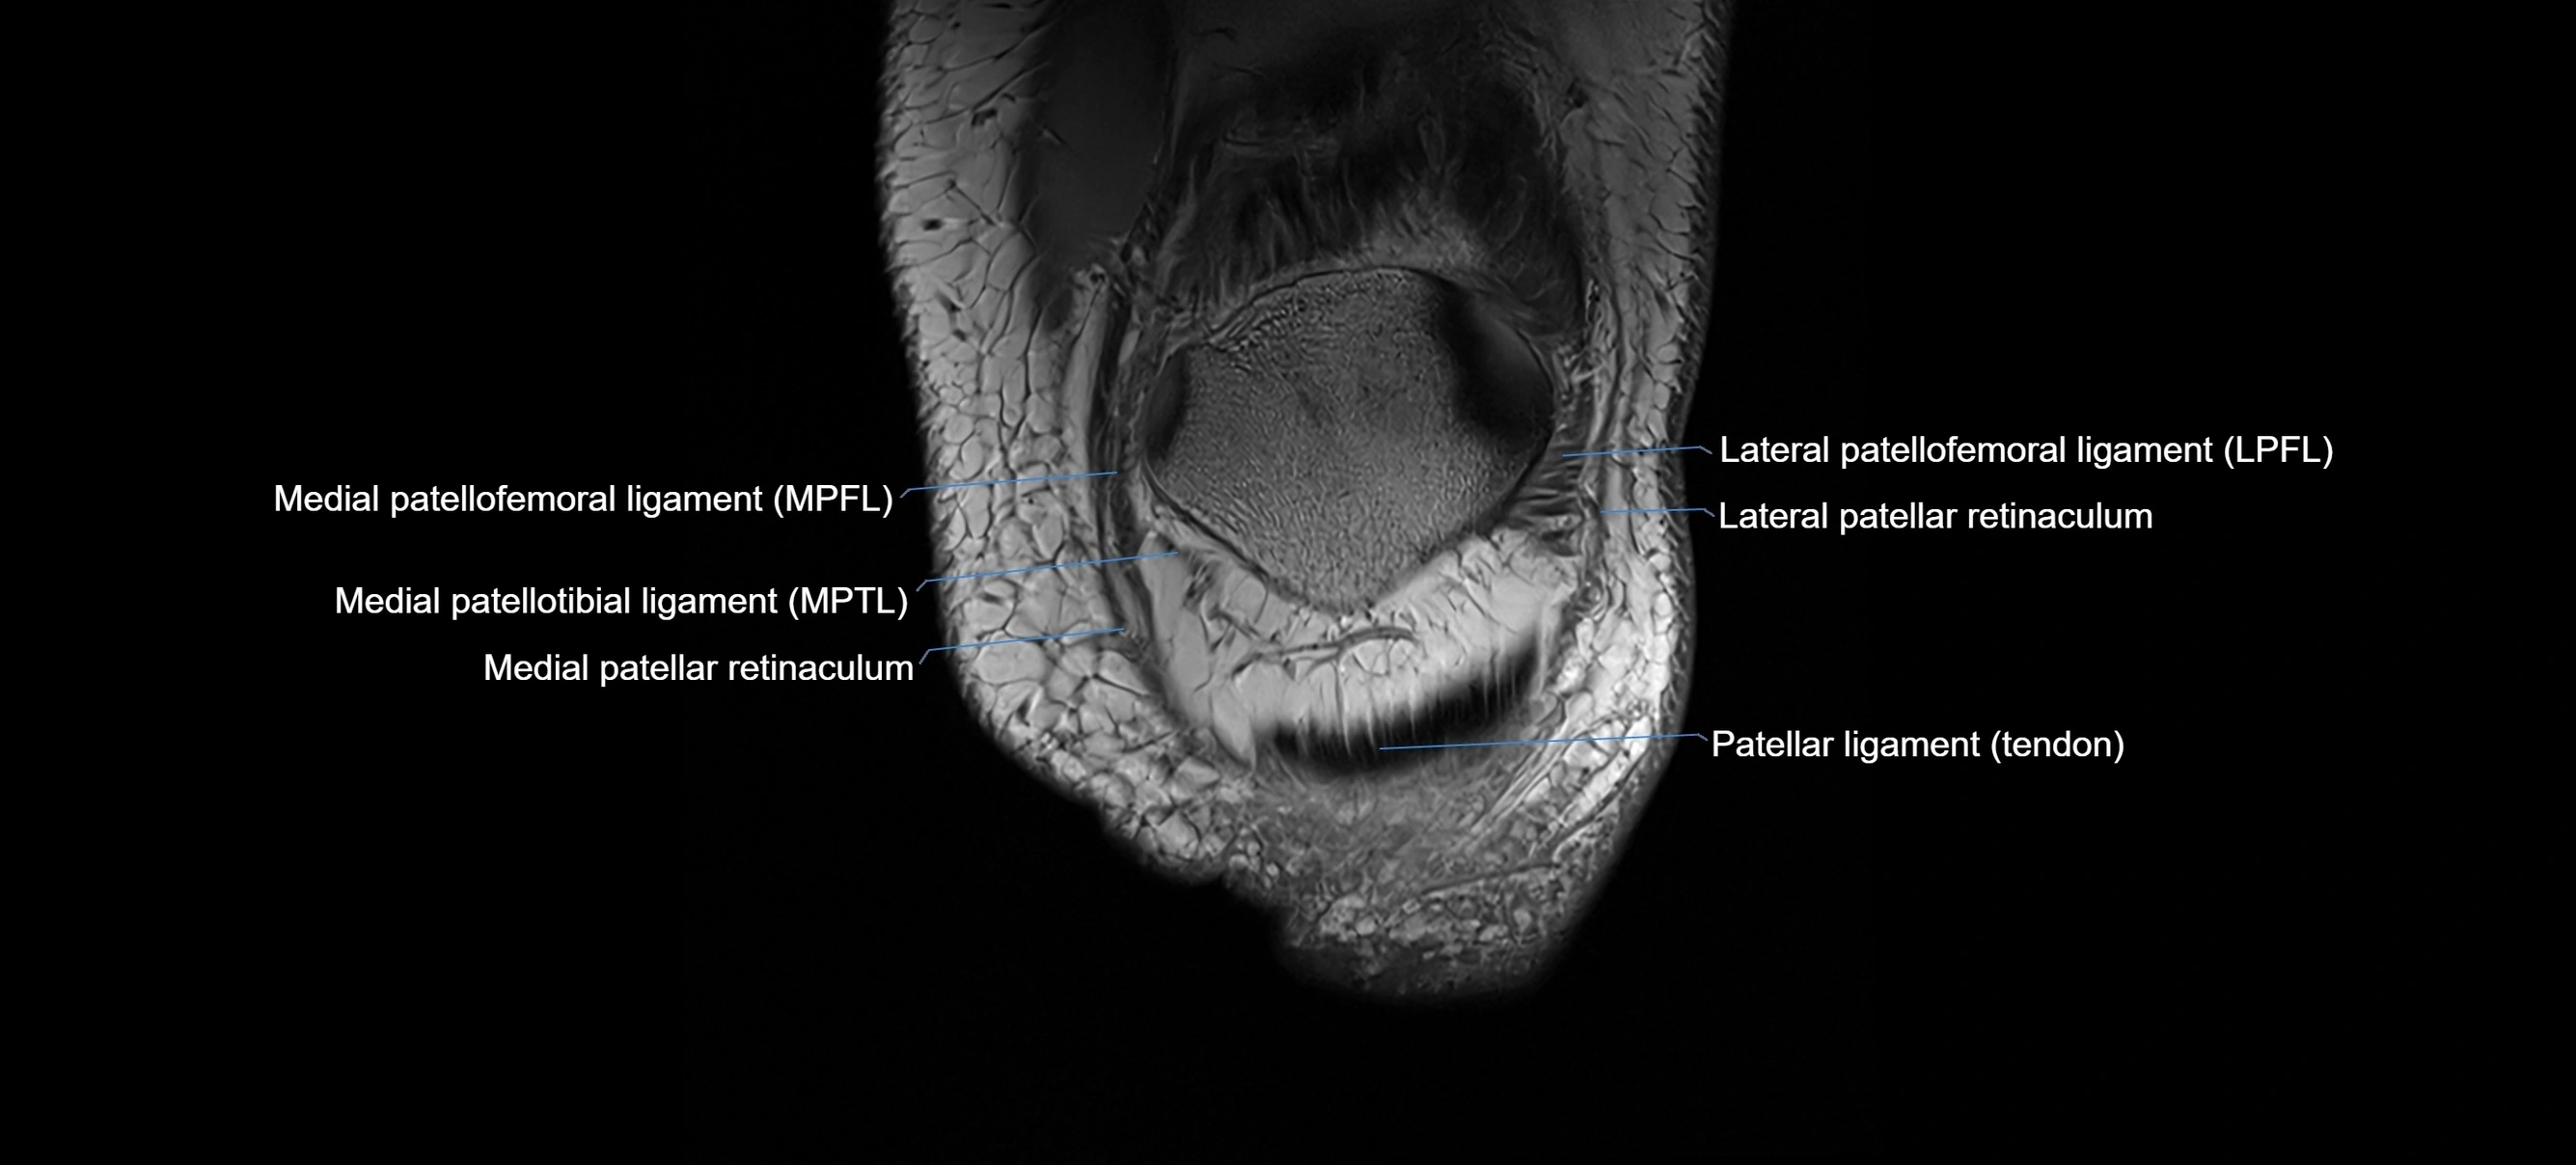

MRI images

image